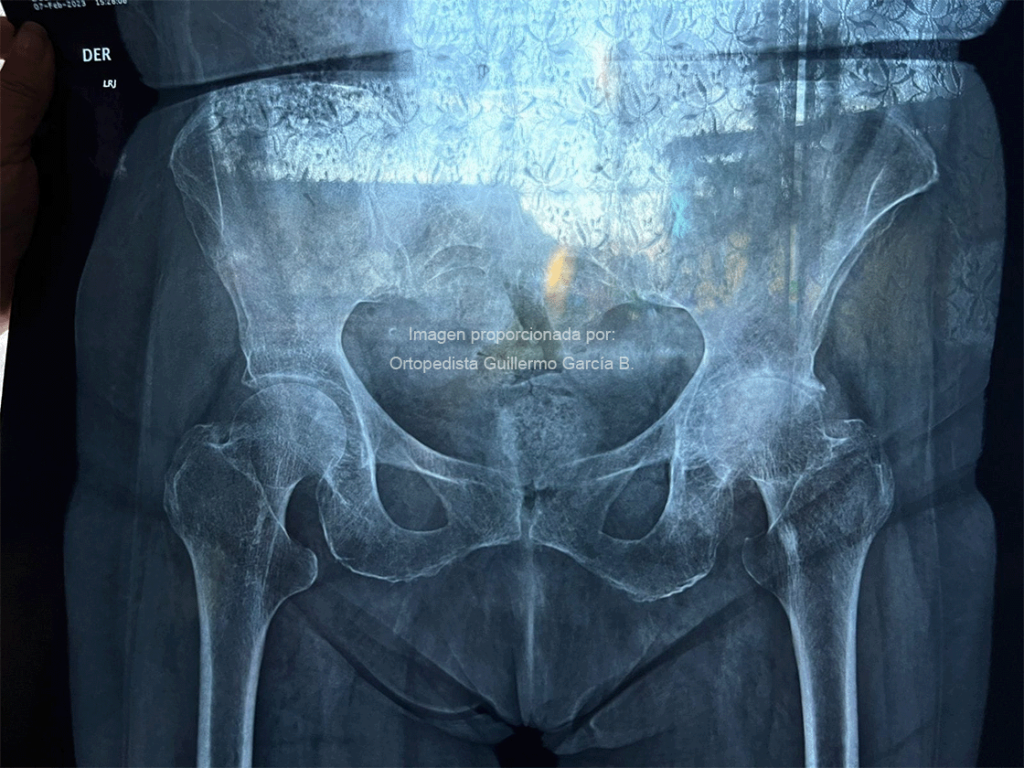

A menudo se piensa que una fractura de cadera es un accidente poco frecuente con una solución simple, pero la realidad es mucho más compleja. En un bajo porcentaje de casos, estas fracturas pueden sanar con tratamiento conservador, siendo la cirugía, con reemplazo articular o el uso de placas, tornillos o clavos, el tratamiento más efectivo. La fractura de cadera se define como la solución de continuidad en el fémur proximal, involucrando la articulación coxofemoral.

- Edad: Pérdida de fuerza y descalcificación de los huesos (osteopenia u osteoporosis).